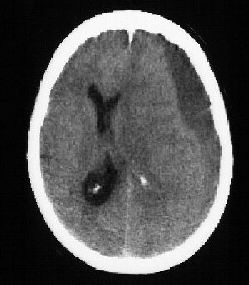

2. The paediatrician suspects shaken baby syndrome and order some

radiological investigations. The following pictures are consistent

with the suspicion: